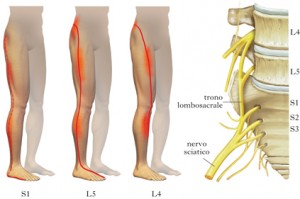

1.腰痛和坐骨神经:这也是腰椎间盘突出症的病人的主要症状,95%以上的突出发生在L4-5或腰5骶1椎间盘。临床上以腰背部的钝痛为多见,平卧位减轻,站立则加剧;另一类疼痛为腰部痉挛样剧痛,不仅发病急骤突然,且多难以忍受,非卧床休息不可,此主要是由于缺血性神经根炎,即髓核突出压迫神经根所致。下肢疼痛多为放射性神经根性疼痛,部位为臀后部、大腿后外侧、小腿外侧至根部或足背部。为了减轻坐骨神经受压所承受的张力而弯腰、屈髋、屈膝位,以减轻疼痛。因此,病人的主诉站立疼痛重而坐位疼痛轻,多数病人不能长距离步行。有关实验结果证实:在腰椎前屈时,椎管内容积增大。当咳嗽、喷嚏、排便等腹压增高时,可诱发或加重坐骨神经疼痛。少数人可有坐骨神经伴腹股沟区疼痛、此系交感神经受刺激引起的牵涉痛。腰椎间盘突出症的病人,在后期常表现为坐骨神经痛重于腰背痛或只表现为坐骨神经痛。

3.麻木:当椎间盘突出刺激了本体感觉和触觉纤维,引起肢体麻木而不出现下肢疼痛,麻木感觉区按受累神经区域皮节分布。